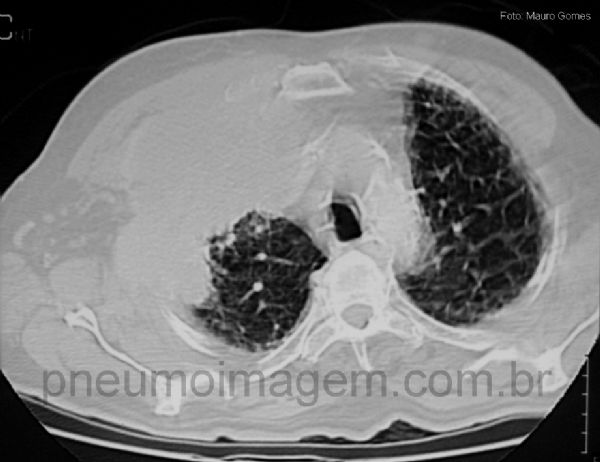

O tumor de Pancoast é definido pela sua localização no ápice do pulmão e não pela sua histologia. Observe a massa envolvendo a parede torácica e levando à corrosão dos três primeiros arcos costais (setas amarelas). Há também a presença de derrame pleural à direita. Chaves: tumor do ápice pulmonar.

The Pancoast tumor is defined because of their location on the apex of the lung and not by its histology. Note the mass involving the chest wall and leading to corrosion of the first three ribs (yellow arrows). There is also the presence of a right pleural effusion.

Keys: lung tumor apex; tumor in the top (apex) of the lung; destructive rib lesion (yellow); destructive chest wall lesion (yellow).

Neste corte observa-se a massa ocupando o ápice pulmonar e envolvendo a caixa torácica, levando ao desaparecimento das costelas. Caracteristicamente o tumor de Pancoast leva à compressão da cadeia simpática cervical e ao desenvolvimento da síndrome de Claude Bernard Horner: miose, enoftalmia, anidrose e ptose palpebral. Quando há o envolvimento do plexo braquial há muita dor no ombro e fraqueza muscular no membro superior.

In this section we see the tumor in the lung apex and involving the chest, leading to the disappearance of the ribs. Characteristically the tumor Pancoast leads to compression of the cervical sympathetic chain and the development of Claude Bernard Horner syndrome: miosis, enophthalmos, anhidrosis, ptosis. When there is involvement of the brachial plexus there is too much shoulder pain and weakness in the arm.